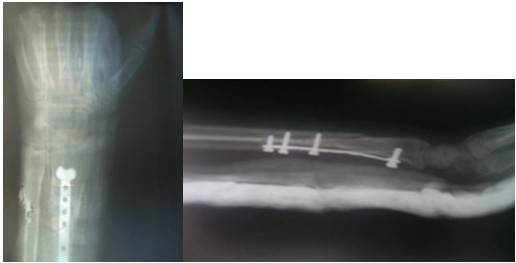

La paciente fue intervenida quirúrgicamente en el salón de urgencias y bajo anestesia general se realizó la reducción y estabilización de la fractura con la preparación de un minifijador RALCA, además, mediante un abordaje volar se realizó la reorganización de los fragmentos fracturarios articulares y la fijación de los mismos con una placa en T de microtornillos de nueve perforaciones. Se colocaron dos tornillos distales para reducir la fractura articular y tres tornillos en el fragmento proximal de la fractura para lograr la estabilidad. (Figuras 3 y 4).

La primera consulta se realizó a los 15 días, se evaluó el estado de la herida, se realizó control radiológico y se retiraron los puntos. Se mantuvo el fijador externo por cuatro semanas hasta que se retiró y se colocó una férula antebraquial por dos semanas más, hasta completar seis semanas posoperatorias y retirar la férula. Durante este tiempo se indicaron radiografías de control para evaluar el estado de la fijación. (Figuras 5 y 6).